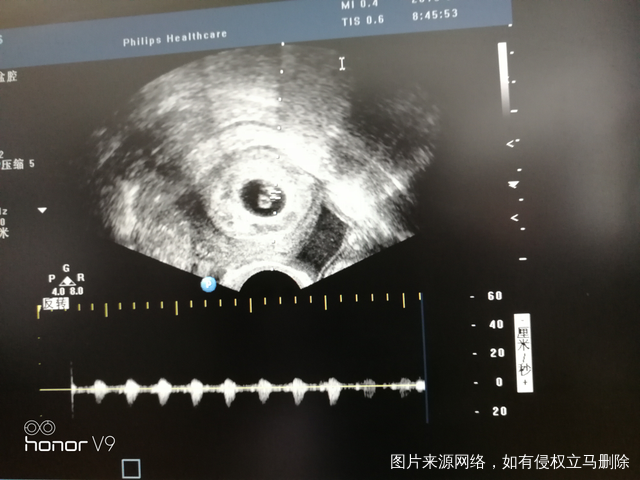

有胎心胎芽了!听到胎心[爱心][爱心][爱心][爱心][爱心]愿一切顺利

有了!听到胎心[爱心][爱心][爱心][爱心][爱心]愿一切顺利